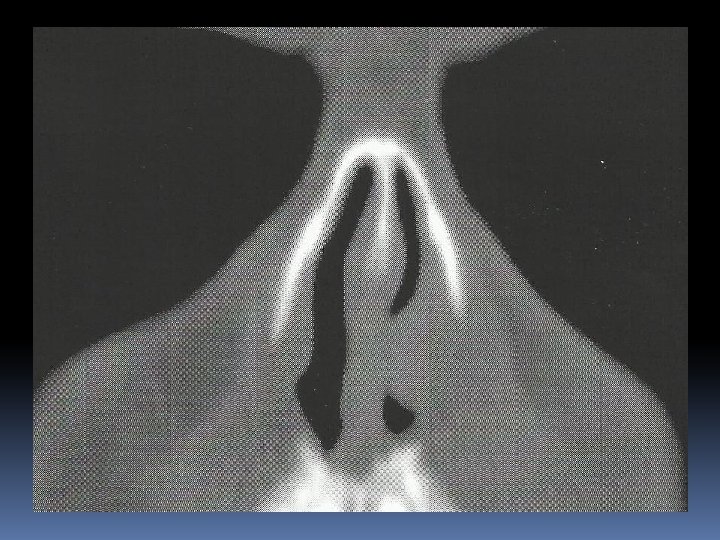

Case Report Paziente di sesso maschile, a. 58, in buona salute Ostruzione nasale omolaterale Neoformazione polipoide carnosa con mucosa integra che occlude anteriormente la fossa nasale sinistra

Intervento chirurgico: asportazione della neoformazione impiantata sulla testa del turbinato inf. in blocco con testa, corpo e parte della coda del turbinato, i margini di resezione appaiono macroscopicamente indenni

Referto istopatologico Neoformazione polipoide impiantata sulla testa del turbinato inferiore, diametro cm. 1 x 2, al taglio appare di colorito biancastro, solida e consistente. Reperti istologici ed immunoistochimici compatobili con melanoma della mucosa della fossa nasale, negativi i limiti di resezione. Sono state eseguite colorazioni con S 100, MART – 1 e HMB 45. Indice di proliferazione 3%